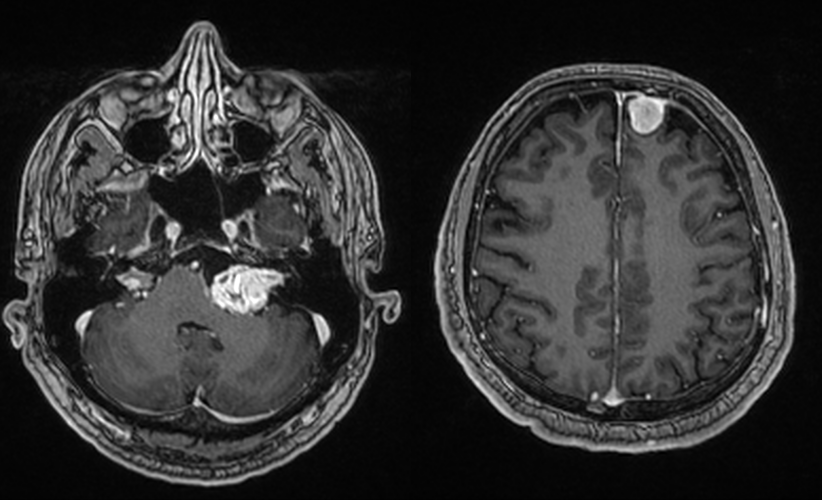

RMN cerebral cu substanță de contrast – Este cea mai precisă metodă pentru diagnostic. RMN-ul evidențiază tumora și arată dimensiunea și localizarea exactă precum și eventualele complicații (hidrocefalie). Pentru tumorile de mici dimensiuni există o secvență specială care vizualizează mai bine nervii cranieni (în funcție de tipul de aparat se poate numi CISS, TRUFI sau FIESTA).

În funcție de aspectul RMN există mai multe clasificări (mai bine zis stadializări) ale schwanoamelor vestibulare, majoritatea având în comun 4 grade:

– Grad I – intrameatal – strict în conductul auditiv intern

– Grad II – intra-extrameatal – tumoră care depășește porul acustic intern

– Grad III – cisternală – tumora se găsește și în spațiul dintre porul acustic și trunchiul cerebral (cisterna ponto-cerebeloasă)

– Grad IV – tumora comprimă trunchiul cerebral

Pe RMN, schwanomul vestibular apare ca o masă nodulară cu priză de contrast, bine delimitată, localizată în spațiul dintre stânca temporală și cerebel, cu origine în porul acustic intern.